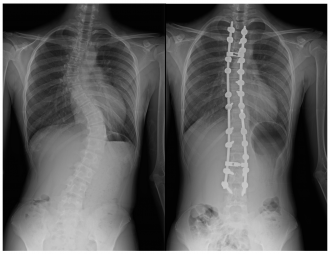

側弯症の手術方法

側弯症の手術方法は、後方矯正固定術(背中から手術する)、前方矯正固定術(お腹側から手術をする)に大別されますが、現在は後方矯正固定術という術式が主流となっています。

後方矯正固定術は、背中の正中部分(真ん中)を切開し、最も傾いている椎体から逆向きに最も傾いている椎体の間にかけて、背骨が見えるように背骨の周囲についている筋肉をはがします。

その後、それぞれの背骨の左右にスクリューを2本ずつ挿入し、それらをロッ ドと呼ばれるチタン合金やコバルトクロム合金のバーで連結することで側弯を 矯正します。各椎体の間にある関節(椎間関節)に、局所の骨や人工骨を移植した後、出血をはじめとする合併症がないことを確認して、傷を閉じます。